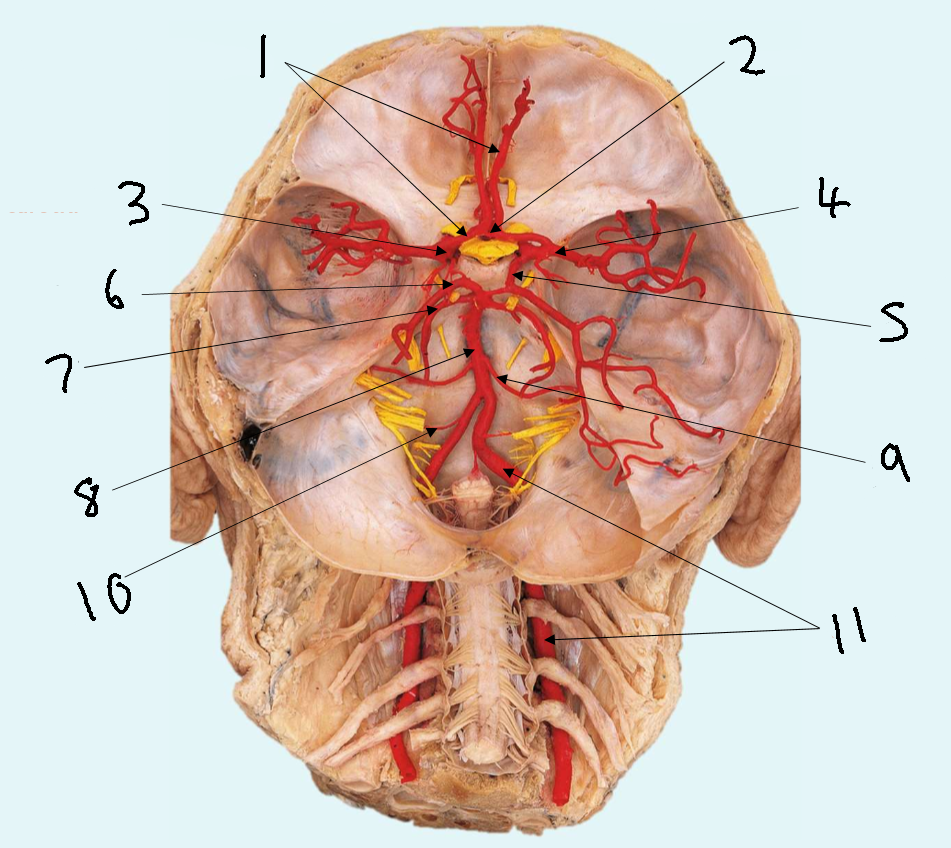

What is 1?

anterior cerebral artery

What is 2?

anterior communicating artery

What is 3?

internal carotid artery

What is 4?

middle cerebral artery

What is 5?

posterior communicating artery

What is 6?

posterior cerebral artery

What is 7?

superior cerebellar artery

What is 8?

basilar artery

What is 9?

anterior inferior cerebellar artery

What is 10?

posterior inferior cerebellar artery

What is 11?

vertebral artery